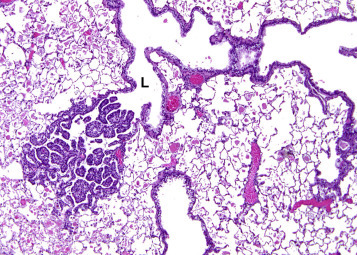

6.3. Bronchial Hyperplasia

Hyperplasia of the bronchial epithelium may occur as a regenerative response secondary to injury or as part of the morphological continuum in response to a carcinogen causing bronchial neoplasms. Inflammation associated with focal hyperplasia suggests that the hyperplasia is secondary, whereas hyperplasia occurring in the absence of evidence of tissue injury may be preneoplastic. This lesion is characterized by increased layers of surface respiratory epithelial cells, usually lacking cilia. The proliferating epithelium may project into the airway lumen and may be papillary with small fronds of epithelium supported by a scant connective tissue core (Figure 23.23 ). Mild nuclear atypia and pleomorphism may be present.

Figure 23.23.

Hyperplasia of the bronchiolar epithelium. The hyperplastic cells form papillary projections into the lumen (L).